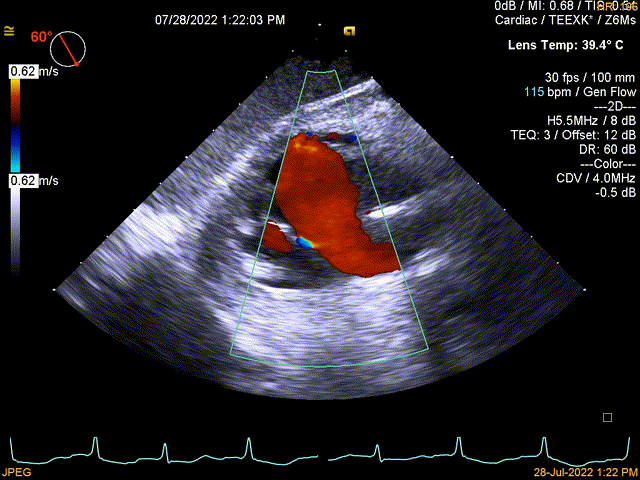

图3:术后即刻TEE

同时其夹子系统继承于申淇淇麟®-经导管二尖瓣夹及可操控导引导管系统优秀设计,具备四个不同型号的夹子及瓣叶分开捕获能力,从而适用于更加复杂多变的三尖瓣解剖。因该患者三尖瓣反流束较宽,瓣叶存在较宽的关闭裂隙,术中很好的利用了瓣叶分开捕获的功能,于后隔瓣区域行瓣膜缘对缘修复。植入一枚长宽夹子后,术后即刻患者反流直接从5级减到2级,患者术后回复良好,自觉症状与临床病情明显改善。